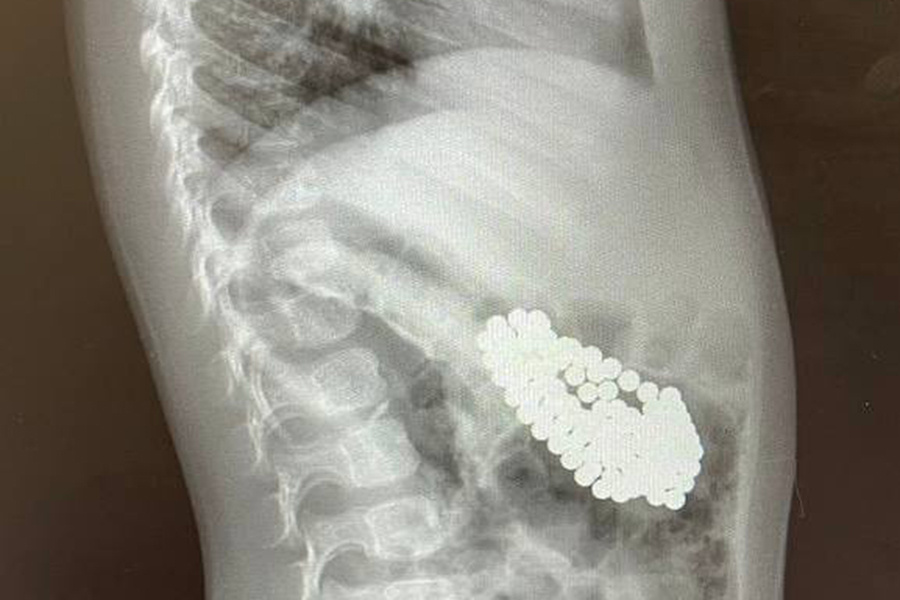

Врачи Центра Леонида Рошаля спасли полуторагодовалого мальчика, проглотившего 130 магнитов и литиевую батарейку. Об этом сообщает пресс-служба минздрава Московской области.

Мальчик поступил в Детский клинический центр им. Л.М. Рошаля с подозрением на проглатывание инородных тел. В ходе обследования в желудке ребенка врачи нашли скопление магнитов и батарейку.

«Магниты сцепились друг с другом, что привело к повреждению слизистой оболочки и образованию язвы. Действовать нужно было быстро. <...> Ребенок глотал магниты в разное время, поэтому некоторые из них уже переместились в кишечник», — рассказал заведующий эндоскопическим отделением Александр Иноземцев.

Металлические шарики достали с помощью специальных инструментов в ходе гастроскопии. Некоторые из них можно было извлечь только хирургическим путем, через маленькие разрезы в брюшной стенке.